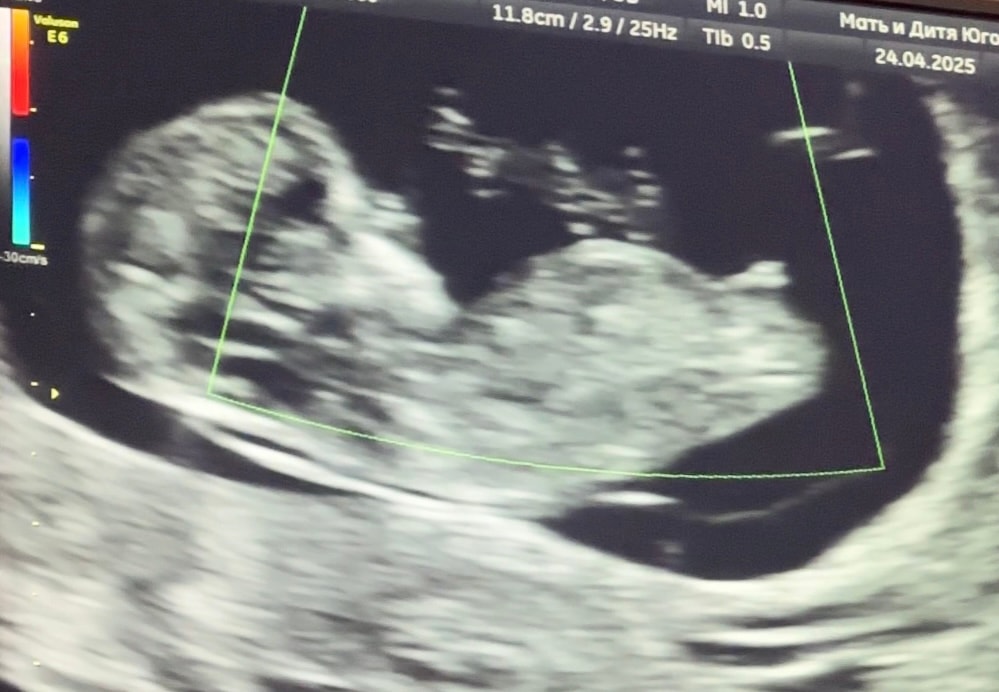

Половой бугорок, 11 недель

Какой хороший снимок. Девочка.

Девочка, половой бугорок пологий.

Kira, имхо! Вы чуть поторопились после 12 было бы лучше видно. Потому что на мой взгляд здесь за оба варианта есть аргументы)

Солнце , скрининг делали сегодня, 11 недель 3 дня)

Kira, не, я про полные 12 недель. Но кмк это всё-таки мальчик)

Солнце , казалось, что прям лежит бугорок горизонтально(